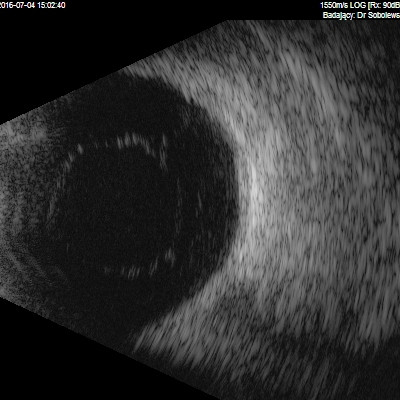

Przedstawiane obrazy ultrasonograficzne® są oryginalne i pochodzą z mojej praktyki lekarskiej